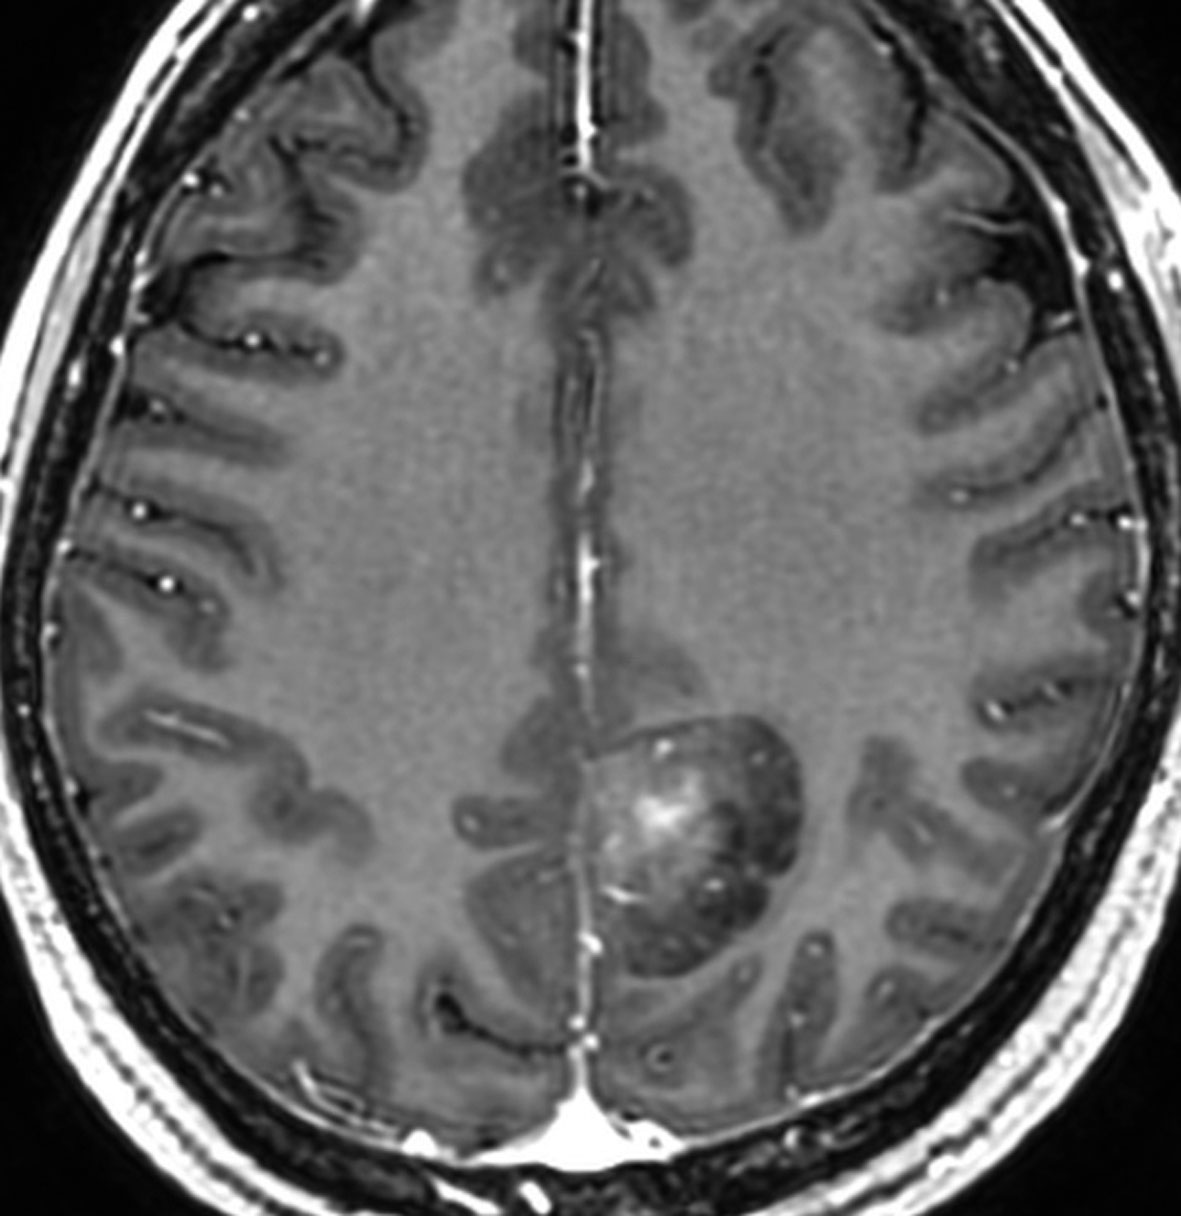

成人の頭頂葉の例

無症状で偶然発見されたものです。CTで石灰化があり,部分的にガドリニウム増強されます。乏突起膠腫グレード2との鑑別が難しい例です。乏突起膠腫より放射線化学療法に治療抵抗性ですから,もちろん治療選択は全摘出です。